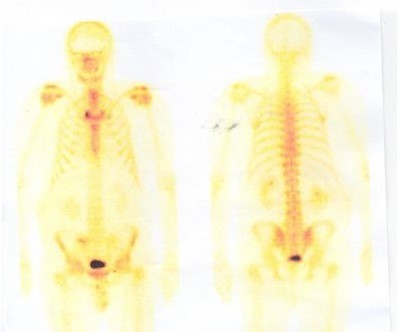

Male, 45 - difficulty with micturition

Skeletal scintigraphy

You are a urologist in an outpatient surgery and a patient has been referred to you by a general practitioner (GP). The GP has referred a 45-year-old man to you for a non-specific micturition disorder that occurred after a cold. The patient has not observed blood in his urine, but this has not been investigated by the doctor. The patient has not yet been followed up urologically, he has not yet been treated.

author: MUDr. Igor Dolan, publicated: 10.01.2018